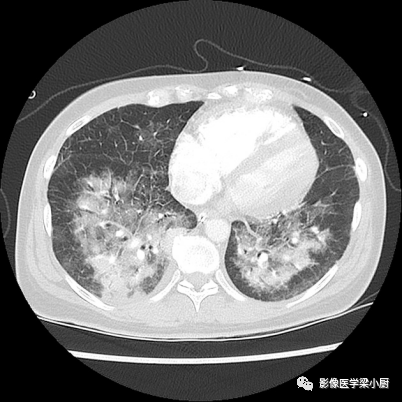

图片图片

间质性肺水肿CT表现

肺泡性肺水肿CT表现